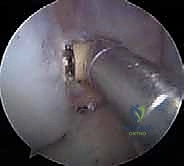

3. المنظار التشخيصي وعلاج الإصابات المصاحبة

يتم إدخال كاميرا المنظار (4K) عبر ثقبين صغيرين جداً في الركبة. يقوم الدكتور هطيف بفحص المفصل بالكامل. إذا كان هناك تمزق في الغضروف الهلالي (Meniscus)، يتم خياطته أو تنظيفه في هذه المرحلة قبل البدء في الرباط الصليبي.

4. حفر الأنفاق العظمية (التحدي الأكبر)

هنا تكمن الصعوبة والتميز في تقنية الحزمتين. بدلاً من حفر نفق واحد في الساق ونفق في الفخذ، يقوم الدكتور هطيف بحفر أربعة أنفاق دقيقة:

* نفقان في عظم الظنبوب (الساق): يتم تحديد البصمة التشريحية الأصلية لحزمة AM وحزمة PL بدقة متناهية، ويتم حفر نفقين منفصلين.

* نفقان في عظم الفخذ: باستخدام أدوات توجيه خاصة ورؤية المنظار الدقيقة، يتم حفر نفقين في موقع المنشأ الأصلي لكل حزمة على جدار الفخذ.

* ملاحظة هامة: يحرص الدكتور هطيف على الحفاظ على أي بقايا سليمة من الرباط الأصلي (Remnant Preservation)، حيث تحتوي هذه البقايا على مستقبلات عصبية (Proprioceptors) تساعد في تسريع التأهيل وتحسين الإحساس الحركي للركبة لاحقاً.